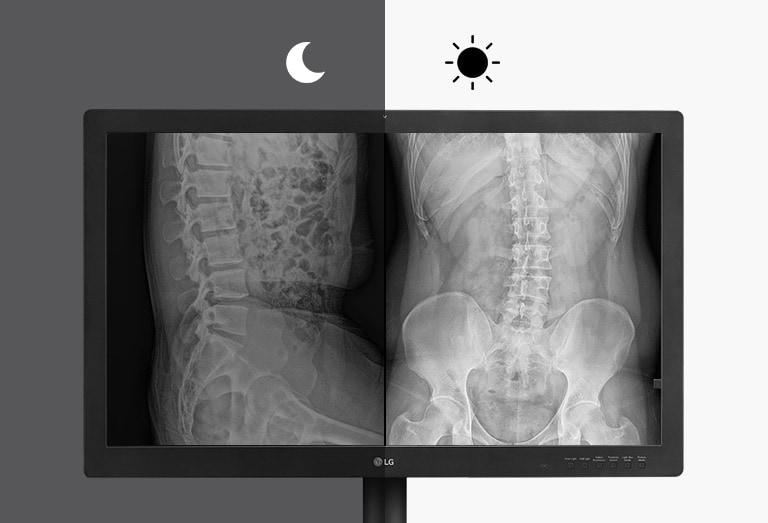

Clear Imaging

Light Box Mode

YES

Auto Luminance Sensor

YES